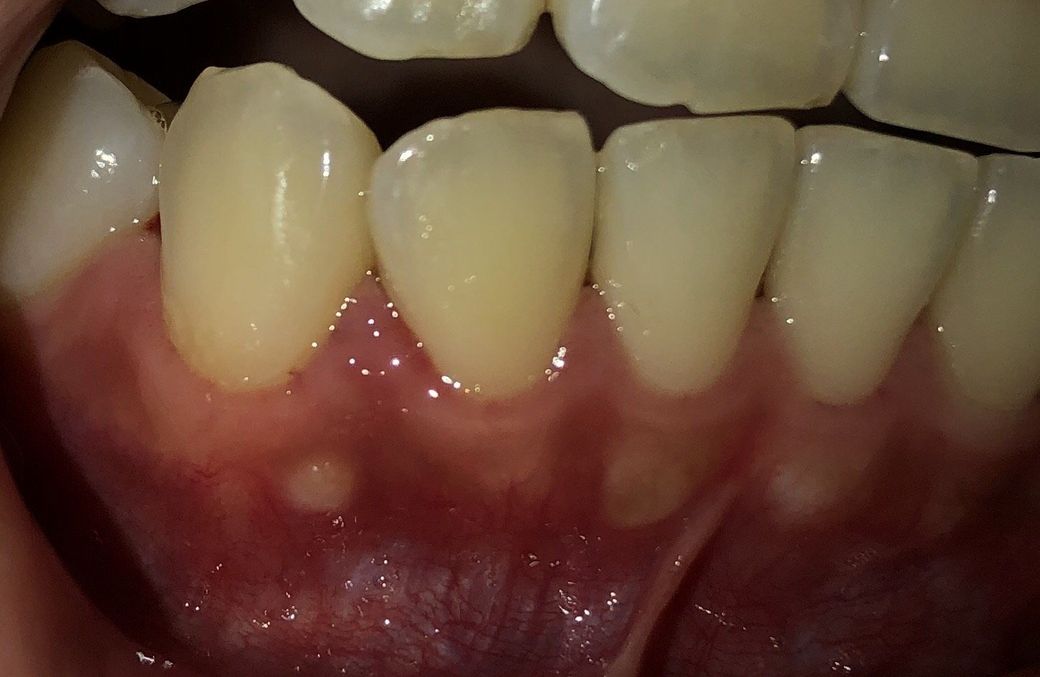

첫번째 사진은 측면이고 두번째 사진은 정면입니다!

두번째 사진에서 1번이라고 써 놓은 저 동그라미가 만지면 약간 딱딱한 느낌이들고 아프지는 않은데 뭔지 신경이 쓰여서요ㅠ 물집같은 느낌은 아니고 정말 약간 튀어나왔어요 저 동그라미가 눈에 보인건 꽤 된 것 같아요

2번이라고 쓴 부분 주위는 유난히 잇몸이 흰색으로 비쳐서 이게 잇몸이 얇아서 치아뿌리가 보이는 건지 아니면 다른 증상인지 궁금해요!

해당부위다 딱딱하다면 뼈가 튀어 나온것일 가능성이 높습니다.

외골증이라고 치아에 가해지는 힘이 강할때 반작용으로 뼈가 자라나오는 경우가 있어요.

잇몸뼈가 돌출된 부분이

얇은 잇몸에 비쳐서 하얗게 보이는 것입니다.

사진에서 보이는 부위는 잇몸뼈입니다. 즉 잇몸뼈가 튀어나온부분에 잇몸이 얇아서 하얗게 보이는겁니다. 크게 걱정할일은 아니니 걱정하지 마세요.